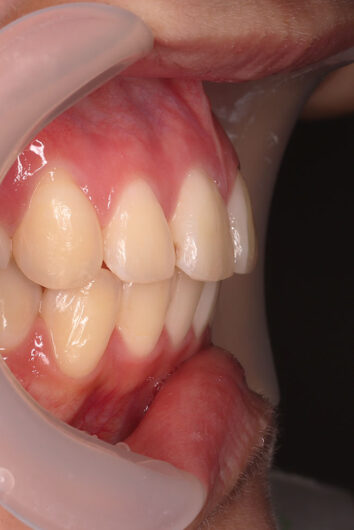

他院から紹介の患者さんです。 前歯、下の歯のガタツキをきれいにしたいということで治療を決断されました。

上顎前歯6mm、下顎前歯2.5mmの前突の状態で、口唇も前突しています。 小臼歯抜歯したスペースを使い、叢生(がたつき)と前突した前歯の後退を目標にしました。 この方も希望により、アンカースクリューは使用せず、通常の顎間ゴムで対処してもらいました。

マルチブラケット 動的治療期間 3年5か月 調整回数29回

治療後は前歯は後退し、前歯の傾斜度も良くなっています。 口唇の緊張感も改善し、エステティックラインも綺麗になりました。